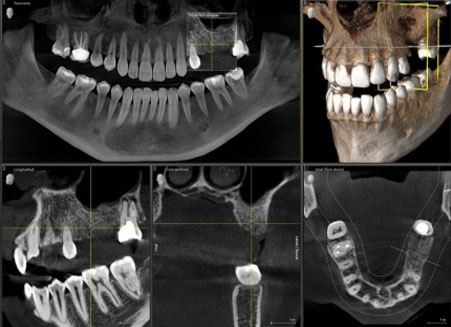

3D OPG

A panoramic radiograph is a panoramic scanning dental X-ray of the upper and lower jaw. It shows a two-dimensional view of a half-circle from ear to ear.

Full Scan

Dental cone beam computed tomography (CT) is a special type of x-ray equipment used when regular dental or facial x-rays are not sufficient.

quadrant-sectional-scan

Quadrant Scan / Sectional Scan

It is helpful in cases where doctor needs to evaluate a particular section or area of intrest. One can eveluate a particular region for implant planning and diagnosis

Mandible / Maxilla

This scan provides full madible evaluation for diganosis and teatment planning for any problem related to mandible, like fracture, cyst, nerve study, imacted tooth,